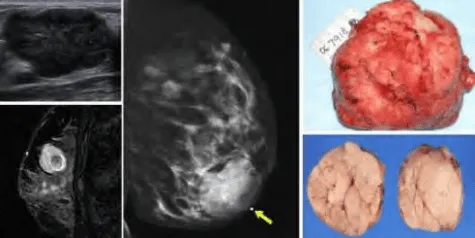

Phần tiêu đề “Cận lâm sàng”Hình ảnh “(Trái, trên) Siêu âm bướu sợi-tuyến: Khối giảm âm, bờ đa cung, đồng nhất. (Trái, dưới) MRI bướu sợi-tuyến: giới hạn rõ, đồng nhất, có vùng thoái hóa. (Giữa) Nhũ ảnh MLO: khối có lớp mỡ mỏng bao quanh. (Phải) Hình ảnh đại thể bướu sợi-tuyến: vỏ bao rõ, mặt cắt phồng đồng nhất”.

Siêu âm:

- Khối giảm âm đồng nhất, bờ rõ, đôi khi có múi, thành trước dày, tăng âm phía sau (posterior acoustic enhancement).

- Hình dạng: Hình tròn hoặc bầu dục, chiều dài lớn hơn chiều ngang (định hướng song song với da).

Nhũ ảnh:

- Khối hình tròn/bầu dục, bờ sắc nét, có thùy nhẹ, không xâm lấn mô xung quanh.

- Thường bao quanh bởi vầng sáng mỏng (halo) do mô mỡ - đặc trưng cho khối lành tính.

- Đôi khi thấy vùng thấu quang bên trong do thoái hóa mỡ.